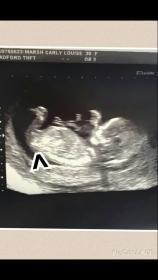

Attachment 21302 is this the nub or Attachment 21302one above?

That's not the nub it's the one above x

OK I wondered that. What do you think?

I''m not seeing a nub captured at all in your image.

Can you definitely not see anything? It's as clear as anything on my scan. Pic. Just don't know which way it's pointing xxc

Theres 2 lines just below its leg xxxx

What the arrow is pointing to low down? I have seen several times on this site that this is something to do with the hip bone.

In pic 3 there is a line which could be a nub and if it is I guess girl.